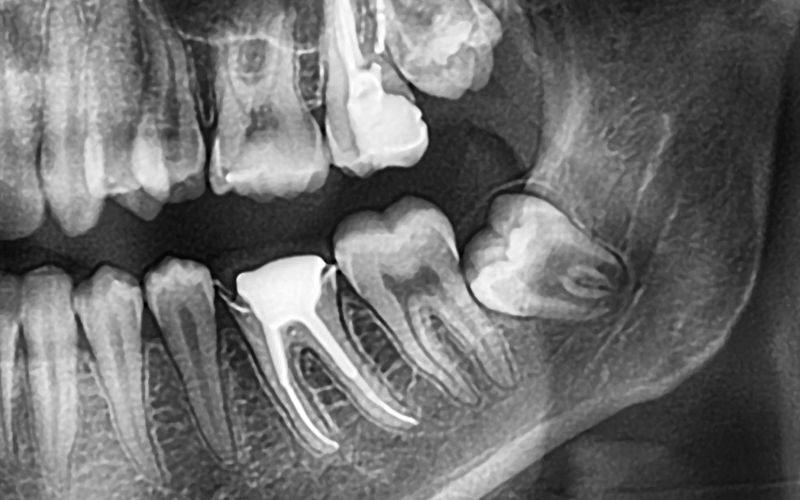

Położenie zęba w kości jest kluczowym wskaźnikiem trudności ewentualnego zabiegu jego usunięcia. W stomatologii stosujemy tzw. klasyfikację Wintera, która opisuje kąt nachylenia ósemki. Zęby mogą być ustawione pionowo, poziomo, a także mezjoangularnie (pochylone w stronę siódemki) lub dystoangularne (odchylone w stronę gałęzi żuchwy). Każda z tych pozycji generuje inne ryzyka i wymaga odmiennego podejścia zabiegowego.

- Ząb zatrzymany i impaksja – sytuacja, w której ósemka jest całkowicie lub częściowo uwięziona w kości. Może to prowadzić do powstawania torbieli zawiązkowych, które niszczą kość przez ucisk.

- Uszkodzenie sąsiednich zębów – ząb rosnący pod kątem może wywierać presję na korzeń siódemki. Taki nacisk często prowadzi do resorpcji korzenia siódemki lub powstania w niej ubytków próchnicowych na powierzchni dystalnej.

Podjęcie decyzji o ekstrakcji w naszym gabinecie poprzedzone jest precyzyjną diagnostyką. Podstawą jest zdjęcie pantomograficzne (OPG), które daje szeroki obraz obu łuków zębowych. W przypadkach, gdy korzenie ósemki na zdjęciu OPG nakładają się na kanał nerwu zębodołowego dolnego, zlecamy tomografię komputerową wiązki stożkowej (CBCT). Dostarcza ona trójwymiarowego obrazu, co pozwala zminimalizować ryzyko uszkodzenia nerwów (parestezji).